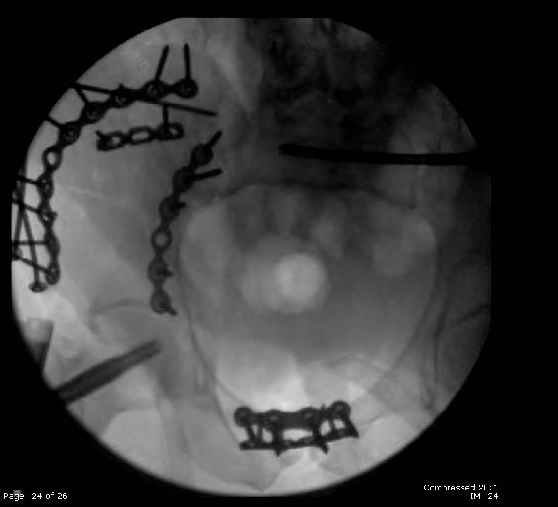

Here are the postop fluoros.

Then 6-hole plate along brim with 1 screw in R sacral ala. Then lagged 2 screws along crest A --> P. finally 10-hole plate along inner aspect of crest. R posterior ilium still a bit stepped off.

Symphysis then 'fine-tuned' & reduced as close as possible to anatomic (but, still with forward rotation of R hemipelvis - or, is it extension?) Accepted that amount of deformity and plated symph

with 4-hole symphyseal plate.

Fluoroed L SI joint and it seemed stable, but wide. So, applied c-clamp to try to squeeze down L SI joint (and note, on the last slide attached, that it's still wide), and got it closer. Single perc Iliosacral screw 40mm thread.

Applied second plate anteriorly on symphysis as I wasn't confident L SI was as stable as it could be and wanted to protect it better.